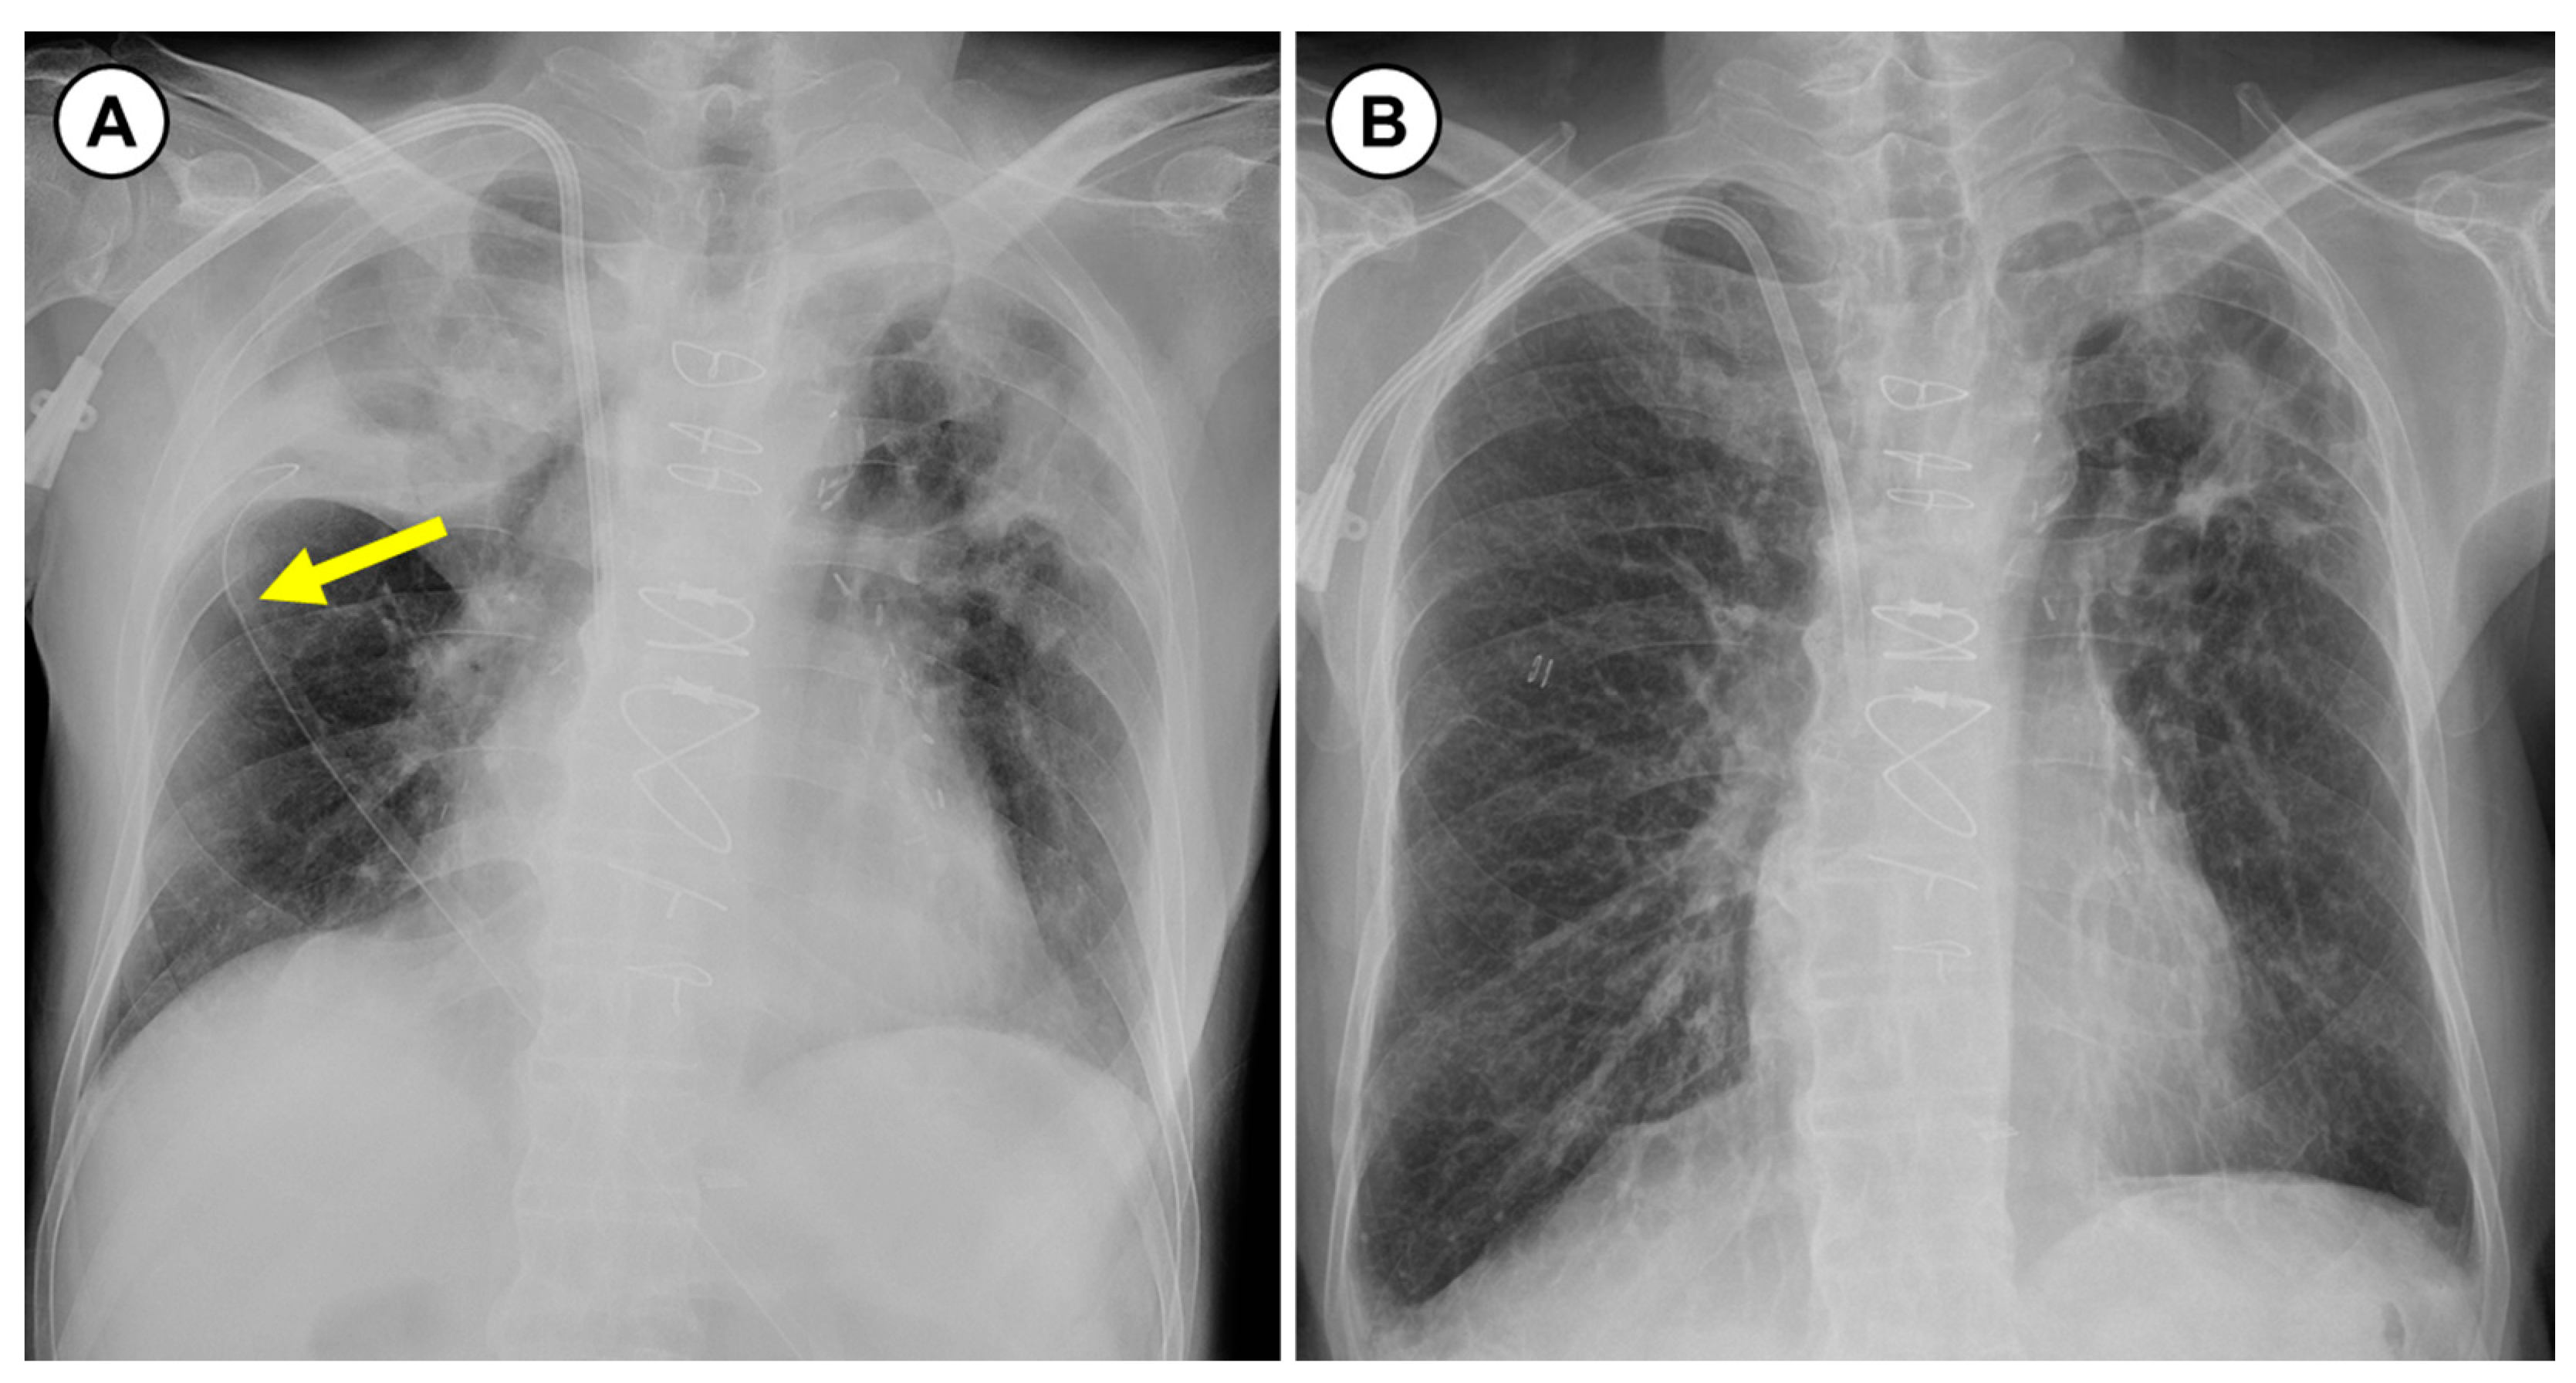

2. Case Presentation